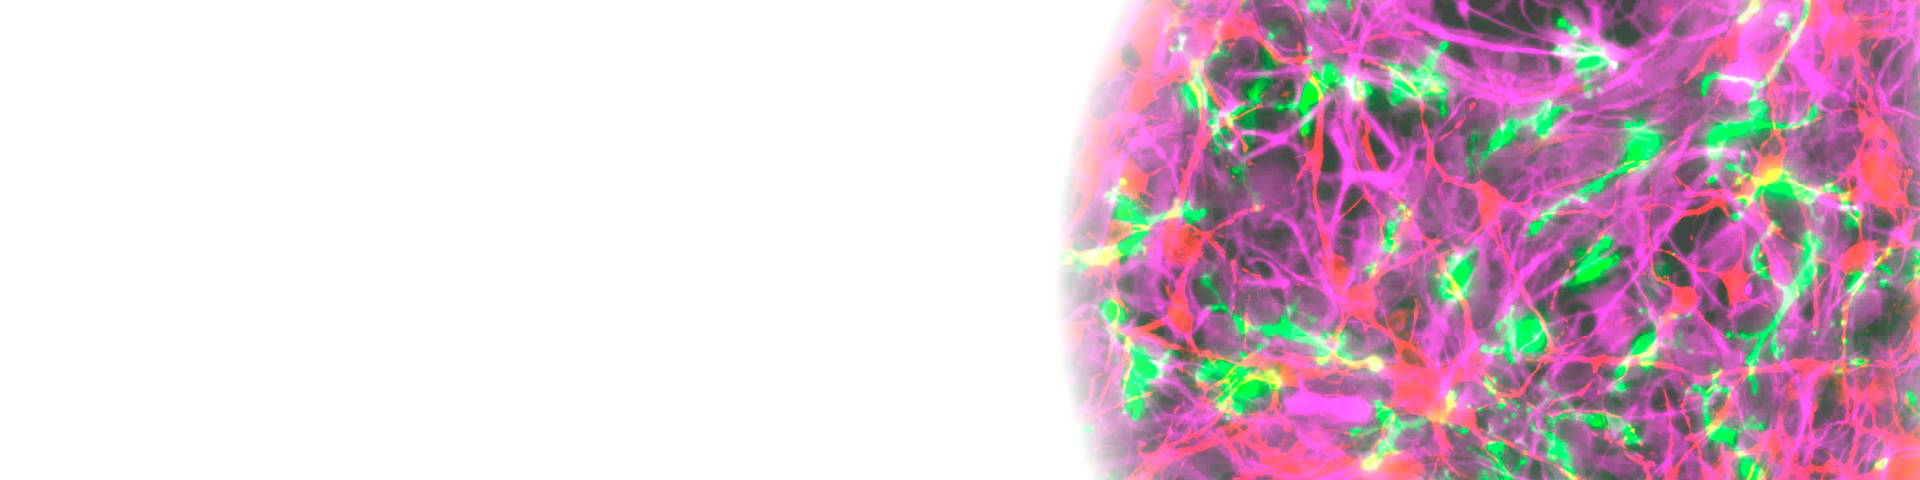

At Fujifilm Drug Discovery Services, we specialize in establishing innovative translational in vitro disease models, focusing on Alzheimer's Disease and Parkinson's Disease, among others. Our ALS model employs chronic oxidative stress-mediated neuronal damage in iPSC-derived iCell® Motor Neurons and links clinical results with targeting ferroptosis and cholesterol biosynthesis, both of which are increasingly recognized for their involvement in ALS development.

Our method of introducing antioxidant deficiency leads to oxidative stress in iCell® Motor Neurons, which results in neurodegeneration. This process is mitigated by Edaravone, a clinically approved ALS therapeutic drug.

Ferroptosis inhibitors effectively prevented neuronal damage caused by gradual oxidative stress, whereas inhibitors of apoptosis or necroptosis did not exhibit similar neuroprotective benefits.

Distal cholesterol biosynthesis inhibitor AY 9944 inhibits neurodegeneration in the chronic oxidative stress model, possibly by leading to an accumulation of 7-DHC, which is a precursor of cholesterol.